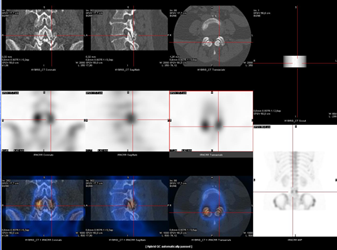

La reconnaissance de ces métastases est cruciale. Or, ces régions anatomiques sont souvent le siège de pathologies coexistantes, telles qu’une maladie dégénérative ou des fractures, qui peuvent rendre difficile le diagnostic différentiel entre pathologie bénigne ou maligne. Dans ces cas, la réalisation d’un SPECT/CT apporte une précision diagnostique améliorée en corrélant les imageries fonctionnelle et anatomique. (fig. 2)

Figure 2 - A gauche: lésion métastatique osseuse - A droite : arthrose.